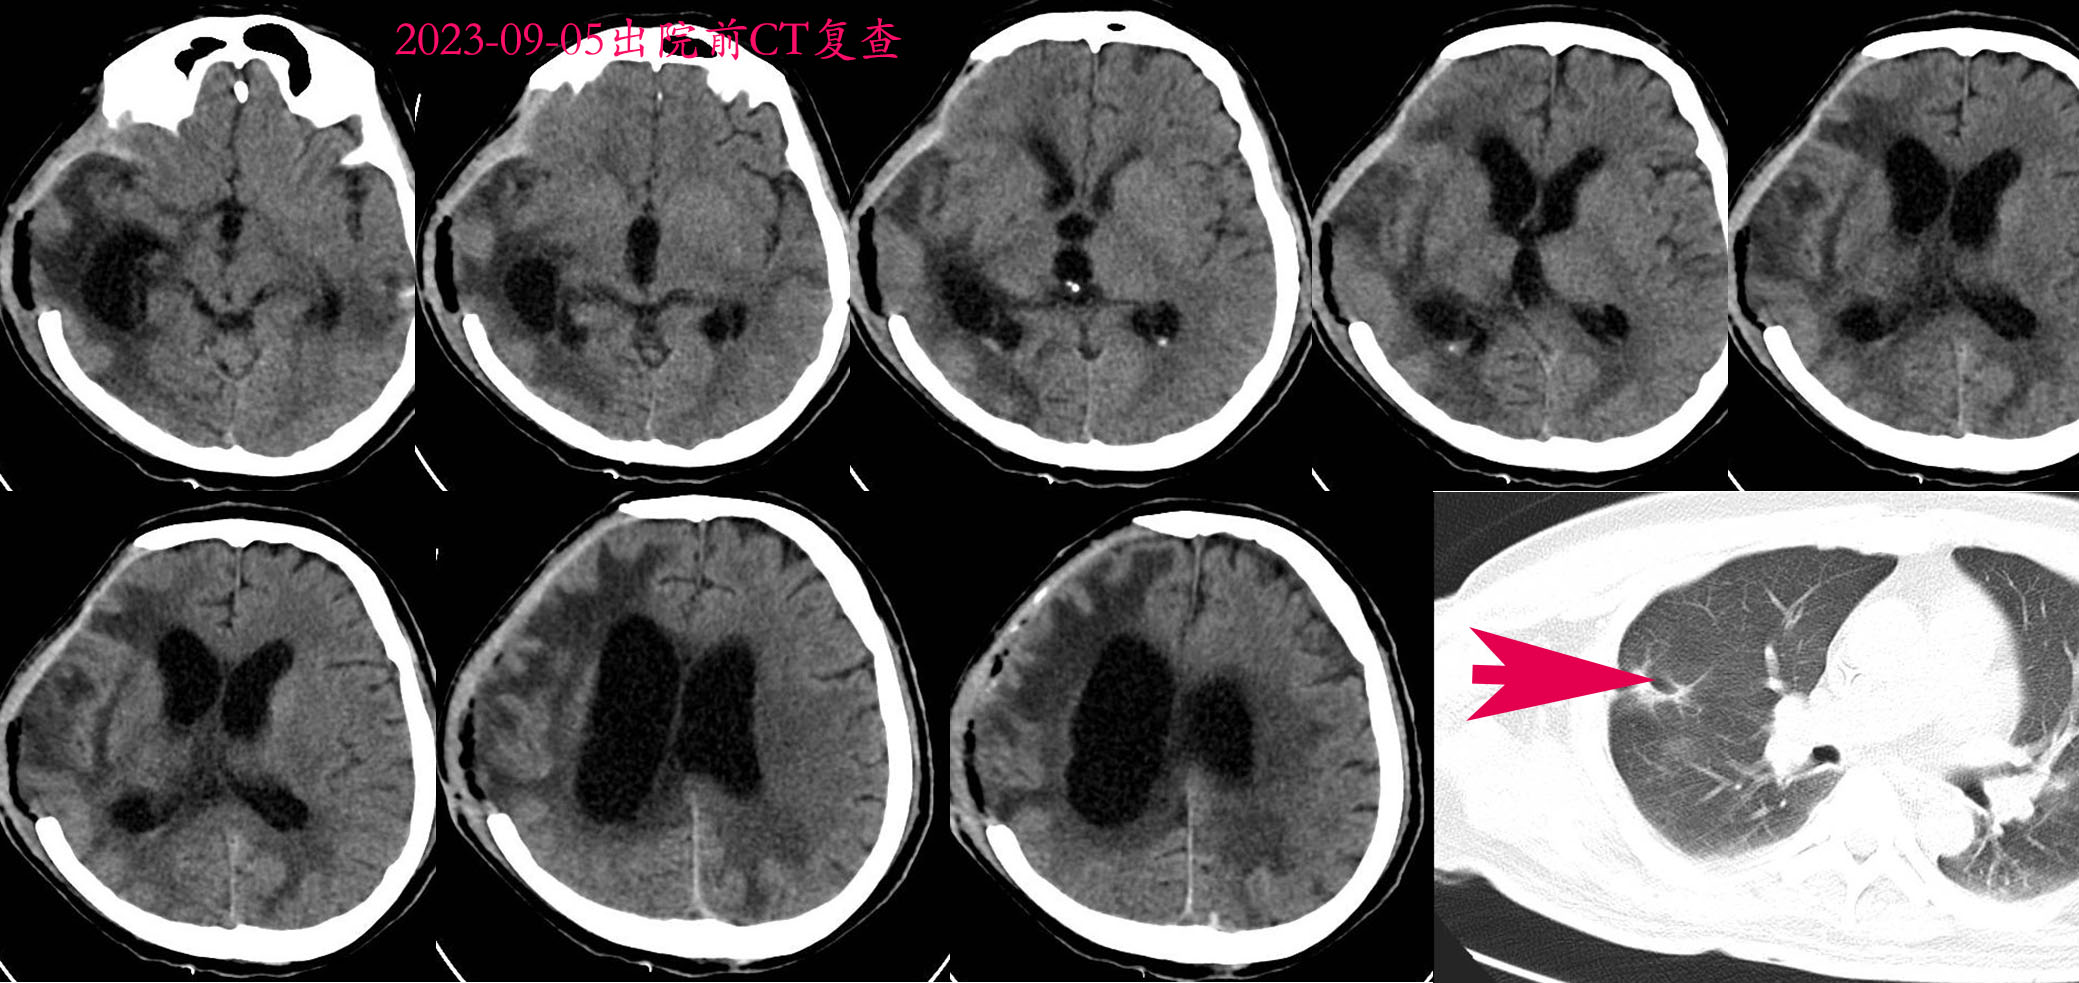

2023-08-05术后第1天CT。

2023-09-05出院时CT复查,可见CT显示肺部病灶明显缩小,考虑肺部脓肿,而非肺癌。患者出院时清醒,但肢体偏瘫,头皮切口尚未完全愈合,转康复医院继续康复治疗,随访3个月后清醒,拔除气管套管,能够讲话。